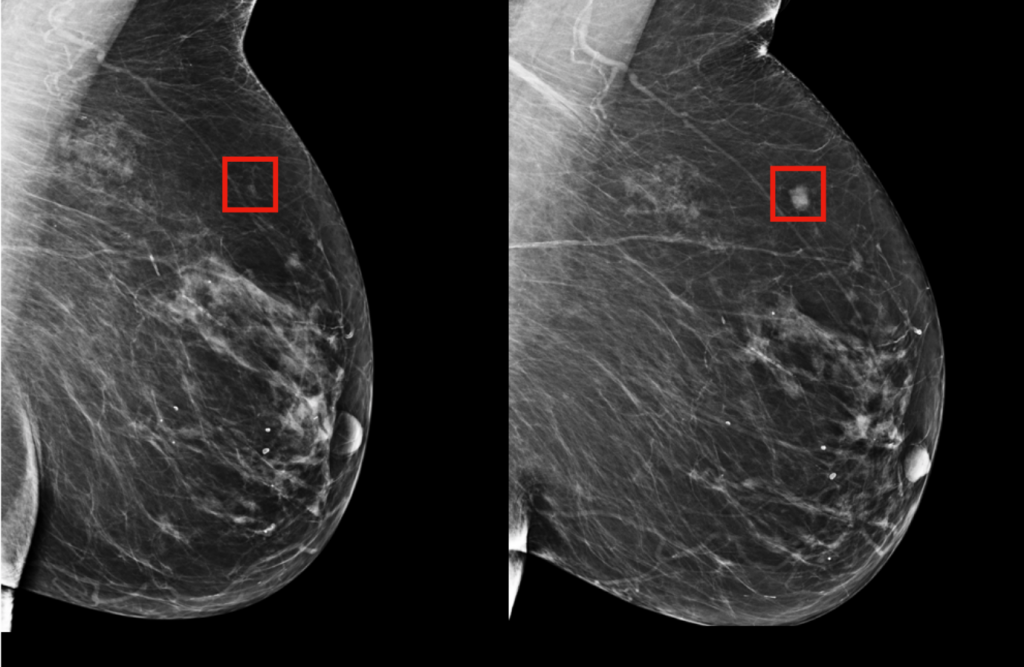

Y es que a pesar de que la atención sanitaria actual se ha centrado en la pandemia, el cáncer de mamas sigue afectando a una de cada nueve mujeres en nuestro país. Si bien el auto cuidado es fundamental para detectar esta enfermedad, la tasa de mamografías realizadas aún es baja a la hora de porcentajes esperados.